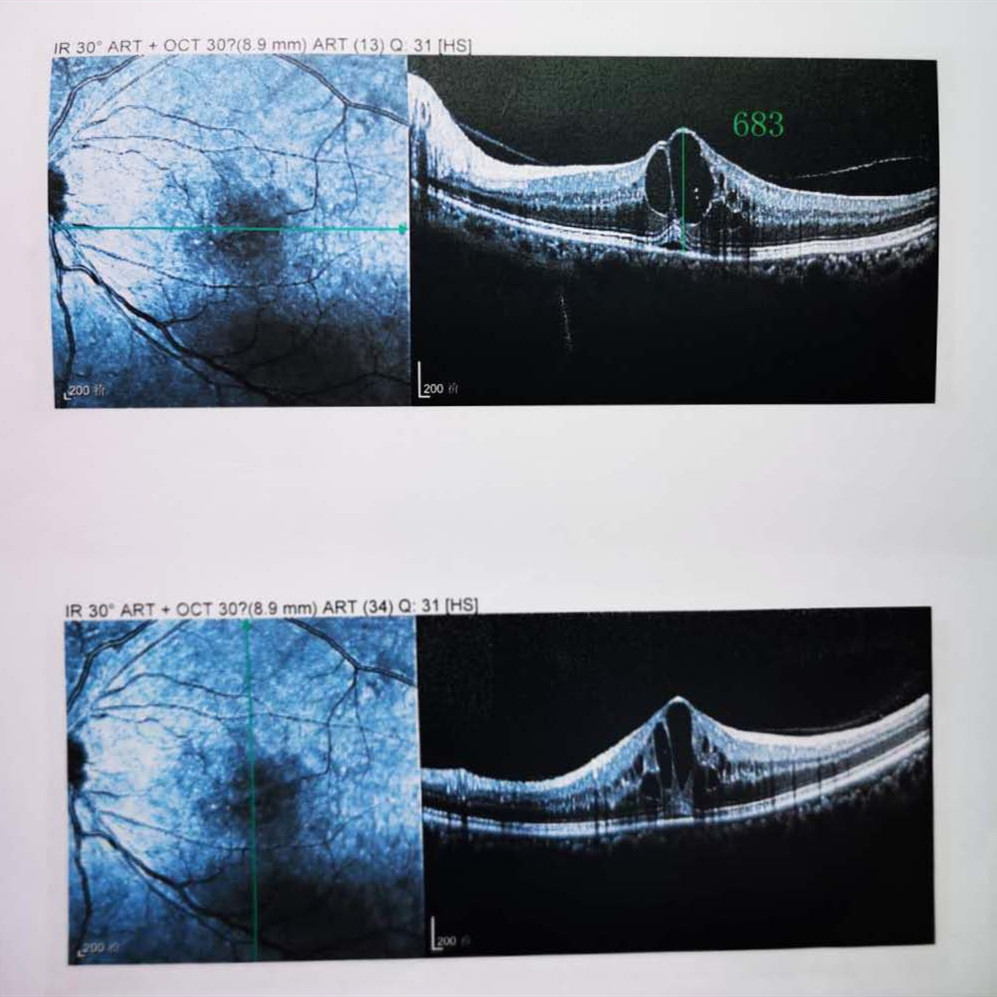

檢查結(jié)果顯示,武先生并沒有近視,右眼視力為1.0,但是左眼視力只有0.4,而且左眼視網(wǎng)膜各分支靜脈迂曲擴(kuò)張,全網(wǎng)膜面見火焰狀出血,黃斑區(qū)高度水腫、滲出,黃斑中心凹厚度約683um。

(武先生初次就診眼底OCT檢查圖)

而正常的矯正視力是1.0,黃斑中心凹厚度在200um左右。

“你這黃斑都腫到正常人的三四倍大了!”廈門眼科中心吳國(guó)基院長(zhǎng)醫(yī)生告訴武先生,“你這是左眼視網(wǎng)膜中央靜脈阻塞伴黃斑水腫,你左眼的視力下降、看東西變形,是因?yàn)槟阕笱垡暰W(wǎng)膜的中央靜脈發(fā)生了阻塞、出血,導(dǎo)致眼底黃斑水腫了。”

那么,武先生的視力恢復(fù)情況如何呢?幸運(yùn)的是,經(jīng)過兩次玻璃體腔注藥術(shù),武先生左眼的黃斑水腫得到明顯改善,視力已經(jīng)恢復(fù)到0.8。

(武先生出院時(shí)眼底OCT檢查圖)